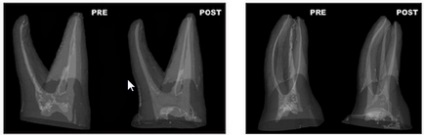

Ábra. 12. A keresztmetszet a gyökér felső kisőrlő ovális gyökérkezelés anatómia (balra) és után (jobbra) szerszám. Mikrokompyuternaya tomográfia.

Ábra. 13. Háromdimenziós rekonstrukció alapján mikroszámítógép tomográfia állkapcsi második premolárisoknál és ovális ívelt gyökérkezelés anatómia. Double Exposure állapot gyökérkezelés a (sárga) és után (piros) szerszám. Ahogy a középső disztális és Bucco nyelvű vetítés mutatja, hogy a anatómiája a gyökércsatorna tartósítva (együtt R. Bedininek és R. Pecci olasz National Institute of Health, Department of Technology és Egészség, Róma, Olaszország).